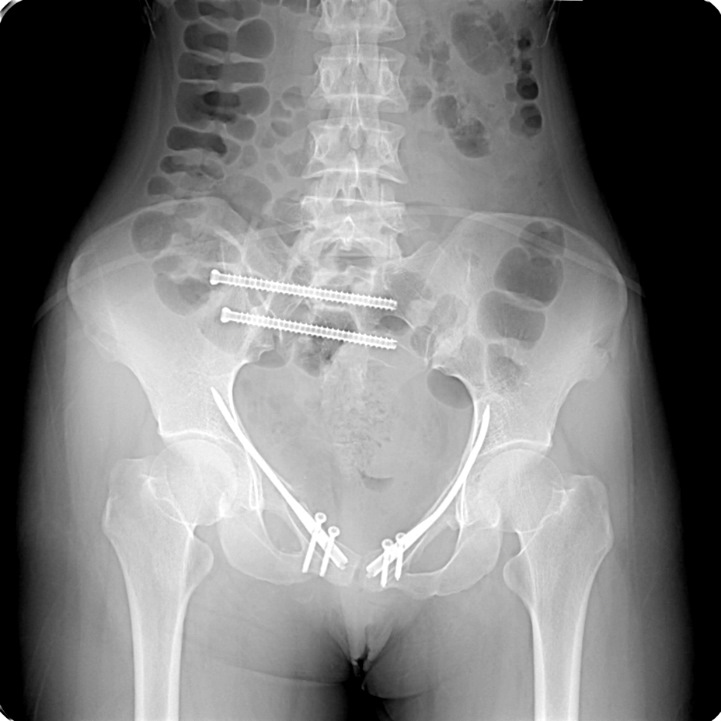

Перелом копчика после

Перелом копчика после 106 фотографий